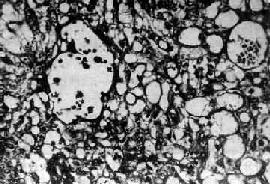

肉眼观,肿瘤多为单侧性,以右侧为多,一般体积较大,平均直径为15~25cm,圆或卵圆形,表面光滑。切面多为实性,质较脆,灰白或粉白色,常有出血坏死及囊性变。镜检,组织形态较复杂及特殊,主要特征有下列几点:①网状结构,是最常见的形态,由星芒状的瘤细胞形成疏松网状结构(图13-23),其中有微型小囊或间隙,囊腔被覆扁平或立方细胞,这种结构类似胚外中胚层结构;②内胚窦样结构,立方或柱状的瘤细胞成单层排列,包绕毛细血管,形成一血管套样结构,这种结构横切面很像肾小球,称为Schiller-Duval小体,这种小体和大鼠胎盘内的Duval内胚窦结构相似,这种结构可能是由卵黄囊衍生演变而来;③多泡性卵黄囊样结构,特征是由扁平上皮、立方或低柱状的瘤细胞形成大小不等的囊腔,其间隔以致密的结缔组织或疏松的粘液样间质,这种结构与胚胎时期的卵黄囊(胚外内胚层)相似;④在瘤细胞内及瘤细胞间隙可见PAS阳性的大小不等的嗜酸性小滴,免疫组化显示这种小滴含有甲胎蛋白(AFP),正常情况下,卵黄囊可合成AFP;⑤可见腺样、乳头状及实体细胞团结构等。

图13-23 内胚窦瘤

呈疏松网状粘液瘤样结构,其中有互相沟通、衬以上皮的腔隙及小囊腔,在瘤细胞内外可见嗜酸性玻璃样小球及基底膜样物